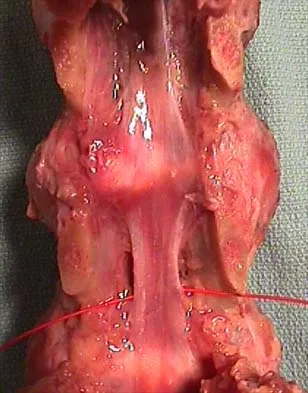

A 19-year-old man has had back pain with activity, especially running in soccer and baseball, for the past 4 months. He denies any history of trauma. Examination reveals no motor weakness or sensory changes in the lower extremities. Range of motion shows increased pain with extension and mild limitation with flexion. A sitting straight leg raising test is limited at approximately 60 degrees bilaterally by back and buttocks pain. Plain radiographs are normal. MRI scans are shown in Figures 13a through 13e. What is the most likely diagnosis?

Explanation